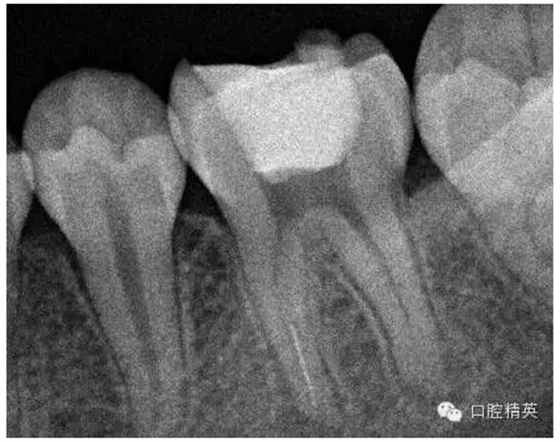

3,術(shù)前左下6近中根管斷針X-P,斷針長度約4MM,根尖慢性炎癥影像。。。